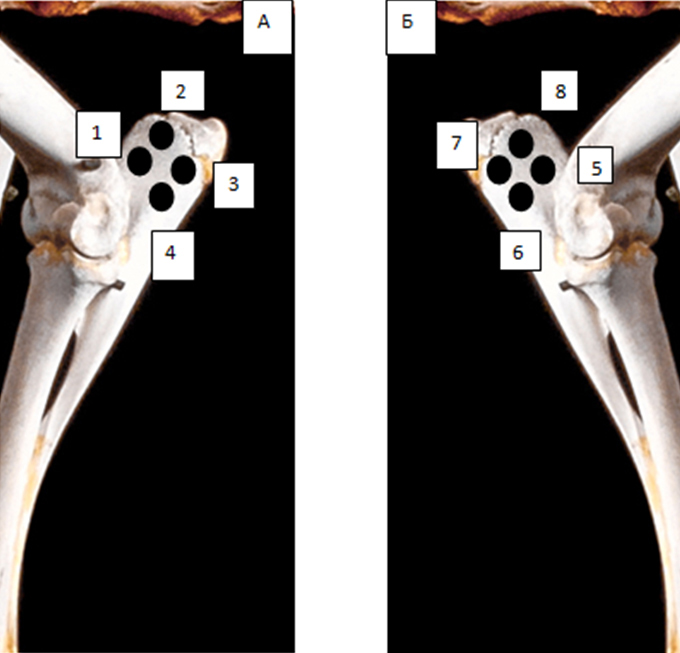

Рис. 2. Поперечный срез альвеолярной кости верхней челюсти человека в проекции отсутствующего премоляра (А) и альвеолярная кость нижней челюсти человека в проекции отсутствующего моляра (Б). 3D-КЛКТ

Учитывая выше перечисленные недостатки, поиск новых областей и способов хирургического доступа для создания экспериментальной модели исследования остеопластических материалов является актуальным. Нас заинтересовало использование в качестве экспериментальной живой модели область локтевого отростка передних конечностей овцы. В доступной литературе нами не встречено упоминаний об использовании локтевых отростков овец с целью формирования костных дефектов для оценки регенераторного потенциала остеопластических материалов. Вероятно, это обусловлено боязнью риска травматизма локтевого отростка в ходе формировании дефекта при использовании классического хирургического инструментария – сверл и фрез большого диаметра. Между тем очевиден ряд преимуществ данной области – схожее анатомическое строение и архитектоника с альвеолярной частью челюстей человека. Локтевой отросток имеет наружный кортикальный слой и внутренний, представленный губчатым веществом с костномозговыми пространствами небольшого размера (рис. 1, 2).